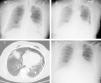

According to our institution's protocol, TBC was performed through a rigid tracheoscope (12, Storz®) under general anesthesia and jet ventilation. A flexible 1.9mm cryoprobe was first passed through a videobronchoscope into the left lower lobe (B9), under fluoroscopic guidance. After confirming correct positioning (tip of the probe perpendicular and about to 10mm from the chest wall), a freezing time of 5s was applied, time after which the videobronchoscope and cryoprobe were removed as a single unit and a bronchial blocker balloon (Olympus® B5-2c) previously placed in the segment was inflated, in order to prevent hemorrhage. The procedure was repeated in the left upper lobe (B4) using a second bronchial balloon, being the first one left inflated in the B9. Only moderate bleeding was verified, controlled with bronchial occlusion and instillation of ice-cold saline. Three lung samples were obtained from the left lower lobe and 2 from the left upper lobe. After deflation of the bronchial blocker balloons and confirmation of absence of bleeding, the procedure was given as concluded. After 2h the chest radiograph revealed a marginal left pneumothorax, considered without indication for chest tube drainage (Fig. 1A). The patient was admitted for vigilance and the subsequent exams showed a pneumomediastinum, small volume bilateral pneumothorax and exuberant subcutaneous emphysema (Fig. 1B and C). An enlarged area along the B9 segmental bronchus suspicious of a bronchus laceration was also evident (Fig. 1C). The patient was polipneic, but alert and oriented, hemodynamically stable and with oxygen saturation with a high flow oxygen mask of 97%. After discussion among Pulmonology, Intensive Care and Thoracic Surgery physicians, it was decided an initial conservative treatment in an intermediate care unit. The clinical evolution under conservative management was favorable, with progressive improvement. After five days the chest radiography had no longer the previous mentioned changes (Fig. 1D), the patient was asymptomatic and was discharged. The histology of the biopsy was consistent with a chronic hypersensitivity pneumonitis and the patient was started on corticosteroids.

(A) Chest radiography 2h following the cryobiopsy showing a marginal left pneumothorax. (B) Chest radiography 4h after the procedure revealing bilateral pneumothorax, pneumomediastinum and subcutaneous emphysema. (C) Computed tomography scan revealing an enlarged area along the lateral basal segmental bronchus (arrow) suspicious of a bronchial laceration. (D) Chest radiography five days after the cryobiopsy showing resolution of the complications.